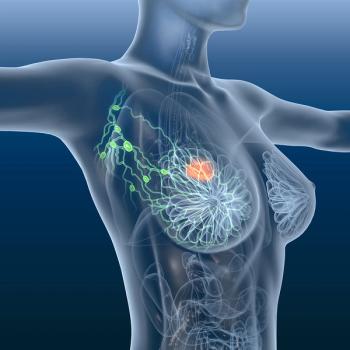

Understanding actionable mutations and educating patients on the safety profiles of targeted therapies are essential for the care of HR+, HER2- mBC.

New therapies in breast cancer, particularly ADCs, present unique safety profiles for nurses to be aware of, according to Erika Hamilton, MD.

Data from a research database link ctDNA positivity in early breast cancer with poorer survival and higher recurrence risk.